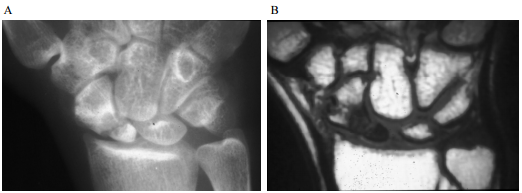

73 14 歲女孩,主訴頭痛、視力模糊,根據此二張注射 Gd-DTPA 的 MRI, T1WI,最可能的診斷是:

(A)cerebellar vermis hemorrhage due to AVM (B)cerebellar vermis medulloblastoma (C)cerebellar vermis hemangioblastoma (D)cerebellar tonsilar herniation